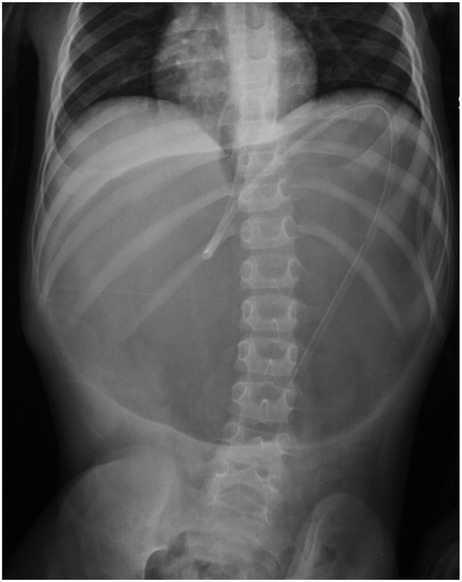

Background Acute gastric volvulus is a rare condition in children, and a delay in diagnosis may lead to gastric ischemia, perforation and even death. It is sometimes associated with wandering spleen, a condition where the spleen migrates from its normal anatomical position due to the absence of fixation ligaments. We report the first case of a patient affected by Pitt-Hopkins syndrome with simultaneous acute gastric volvulus and wandering spleen. Case report A 6-year-old male affected by Pitt-Hopkins syndrome, was urgently referred for acute abdominal pain and 24-hour history of non-bilious and non-bloody emesis. X-ray showed a massive gastric dilatation. Upper gastrointestinal series (UGI) revealed a gastric outlet obstruction. An emergency laparoscopy revealed a gastric mesoaxial volvulus with hypotonic wall with no sign of ischemia or perforation associated with a wondering spleen. Gastropexy was performed by anchoring the gastric greater curvature to the anterior abdominal wall covering the spleen in a good position in the left upper abdomen, completely covered by the gastric fundus. The patient made uneventful recovery and was completely asymptomatic. Conclusion To our knowledge, this is the first case of simultaneous gastric volvulus and wandering spleen in a patient affected by Pitt-Hopkins syndrome. Laparoscopic gastropexy is an easy procedure and combines the advantages of all surgical techniques adopted in previous eras.